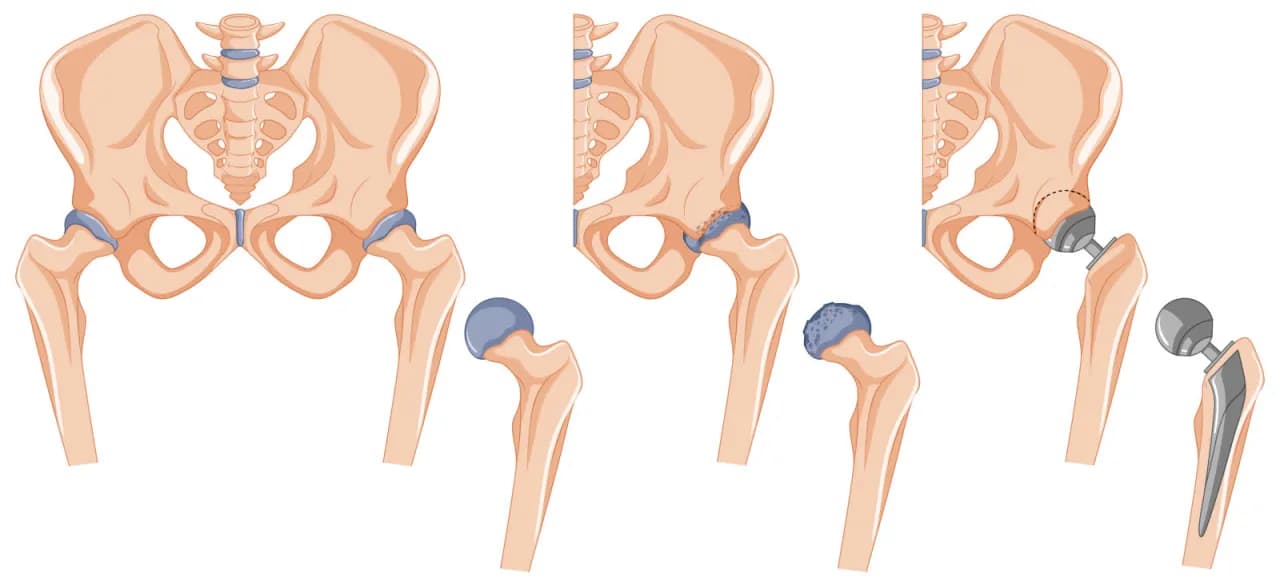

Kiedy rehabilitacja po endoprotezie biodra: co musisz wiedzieć?

Dowiedz się, kiedy rehabilitacja po endoprotezie biodra się zaczyna, jakie są jej cele oraz jakie ćwiczenia pomogą w powrocie do pełnej sprawności.

Kiedy rehabilitacja po endoprotezie biodra: co musisz wiedzieć?

Dowiedz się, kiedy rehabilitacja po endoprotezie biodra się zaczyna, jakie są jej cele oraz jakie ćwiczenia pomogą w powrocie do pełnej sprawności.